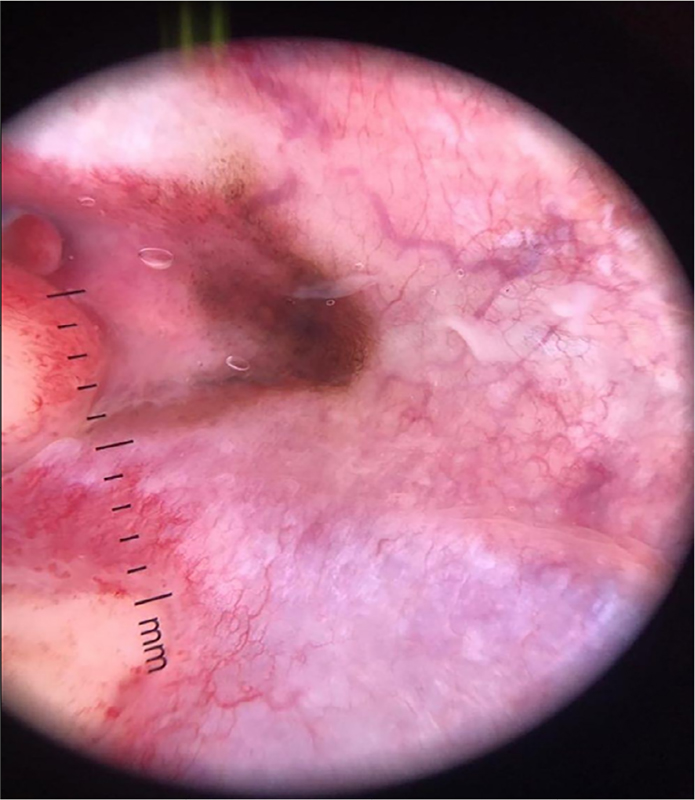

The patient underwent dermoscopy, a method for visualizing the structures located below the stratum corneum, being characterized as a hyperpigmented melanocytic lesion (Figure 2).

Figure 2 Dermoscopy (10x magnification): presence of atypical pigmented network with irregularly distributed spots, pigmented areas without structure (blotch), regression area, and bluish gray veil. Due to the suspicion of malignancy, an incisional biopsy of the lesion was performed.